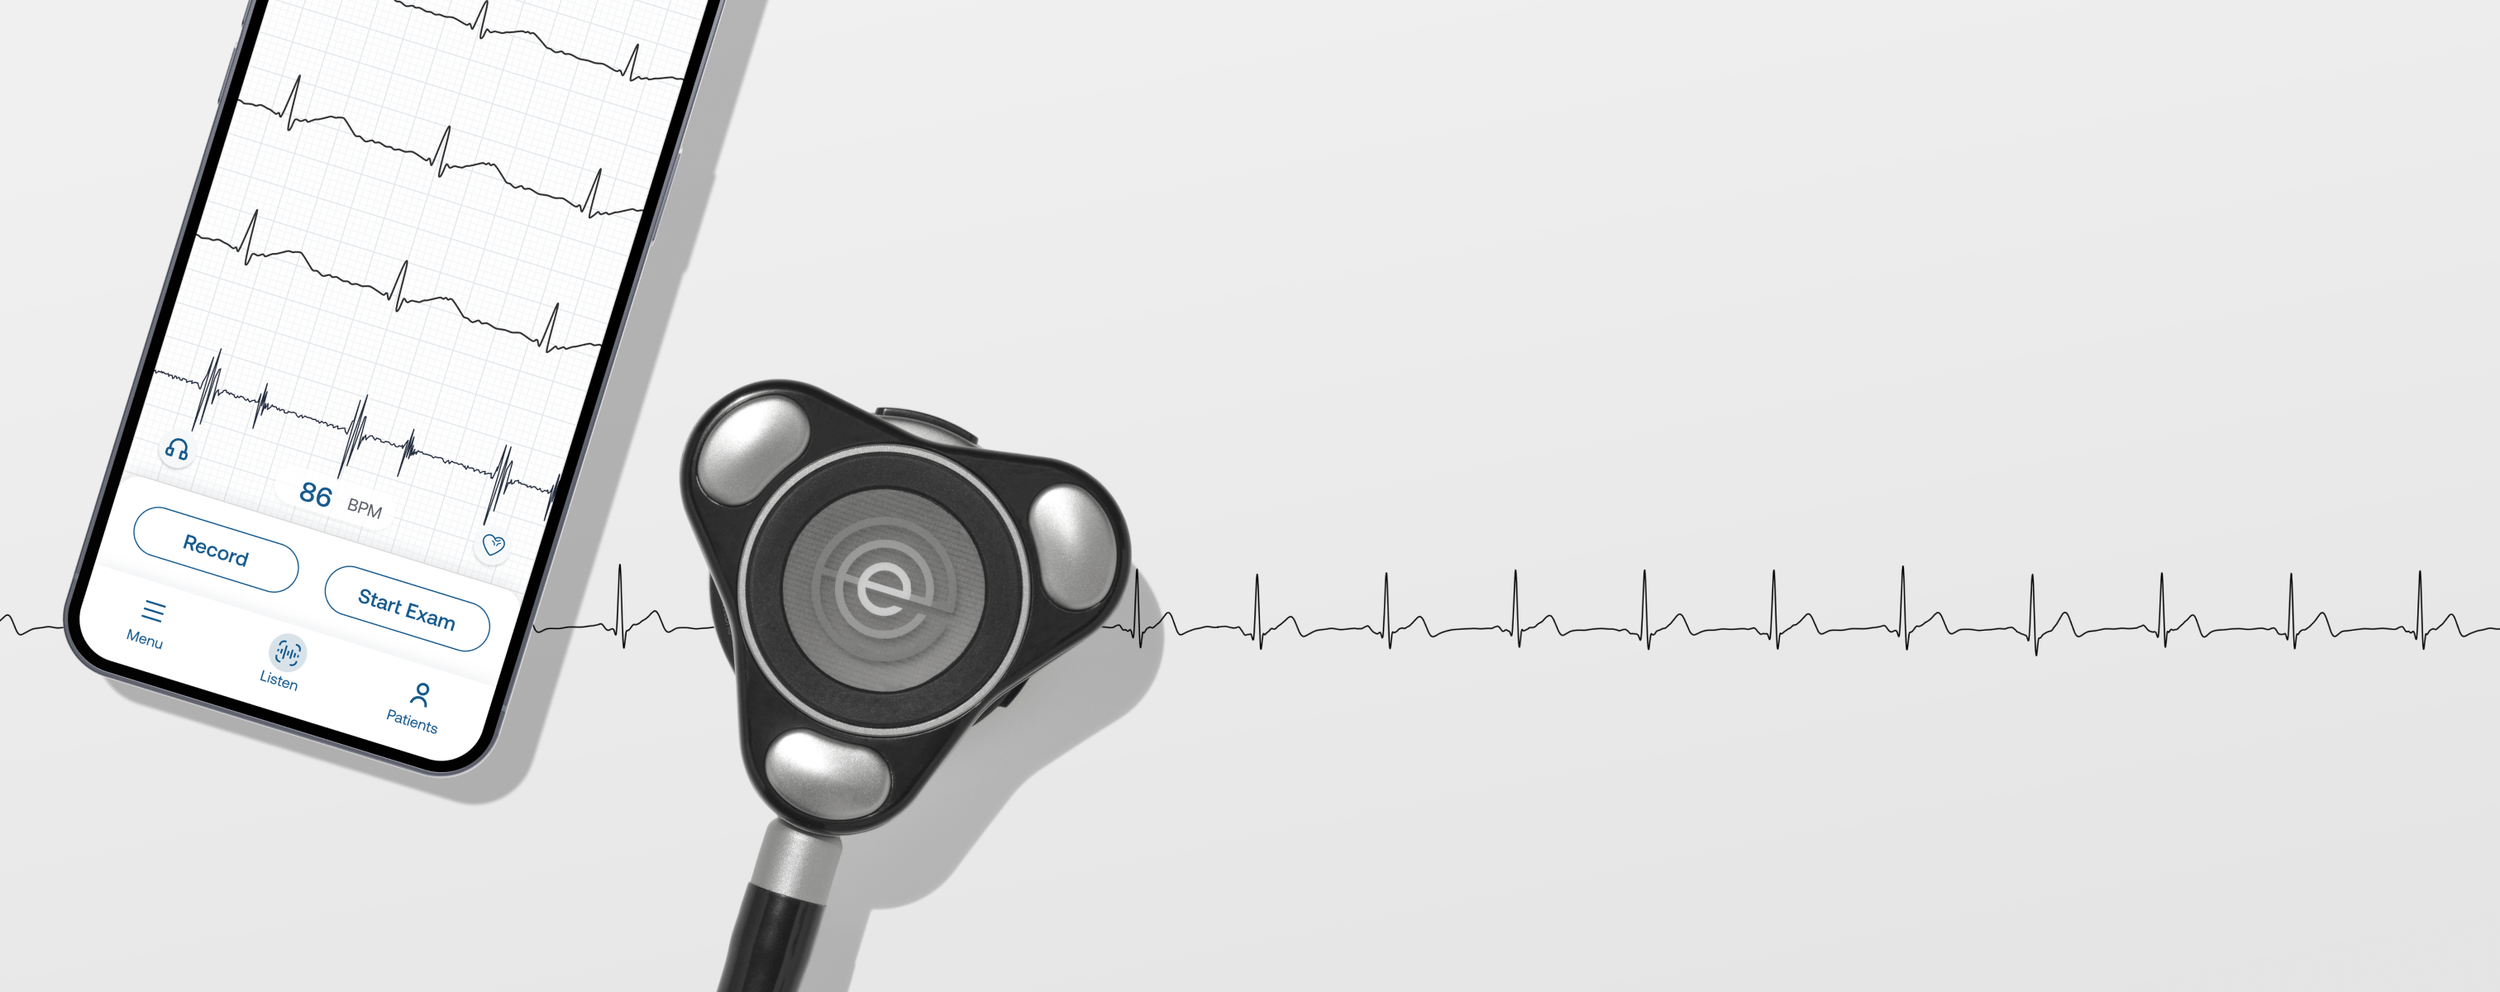

Patient data, exam insights, device settings, and more are visible right at your fingertips.

Patient data, exam insights, device settings, and more are visible right at your fingertips.